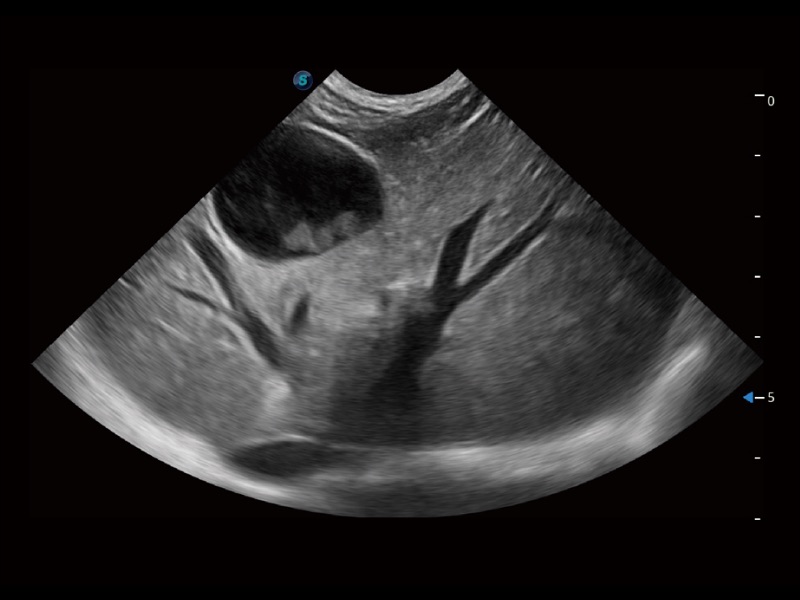

大型犬、馬科、農(nóng)場(chǎng)動(dòng)物及大型異寵動(dòng)物

ProPet 70 全新的動(dòng)物超聲智能軟件和豐富的探頭群,為動(dòng)物醫(yī)生提供了高清晰度和精細(xì)分辨率的圖像,無(wú)論在寵物、馬科、畜牧還是實(shí)驗(yàn)室動(dòng)物等應(yīng)用中都可以輕松應(yīng)對(duì),為您的日常工作帶來(lái)滿意的體驗(yàn)。